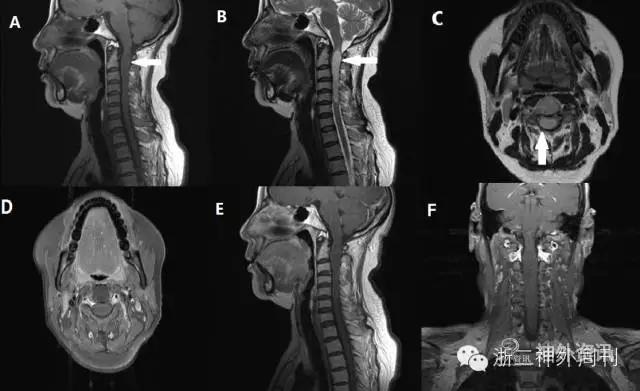

图1. 门诊颈椎增强MRI:颈1-5水平脊髓增粗,内见管状稍长T1长T2信号影,边界清,范围约62mm*10mm,呈偏心性生长,增强(图D-F)后未见强化。

科室术前讨论,该患者MRI显示肿瘤呈偏心性生长,边界清晰,且无明显强化,诊断考虑低级别星形细胞瘤可能大,室管膜瘤待排。由于肿瘤占位明显,患者已有明显的功能障碍,手术指征明确。经完善术前准备后在术中电生理监测下行颈髄髓内肿瘤切除术。手术经过及术中所见如下(图2,3)